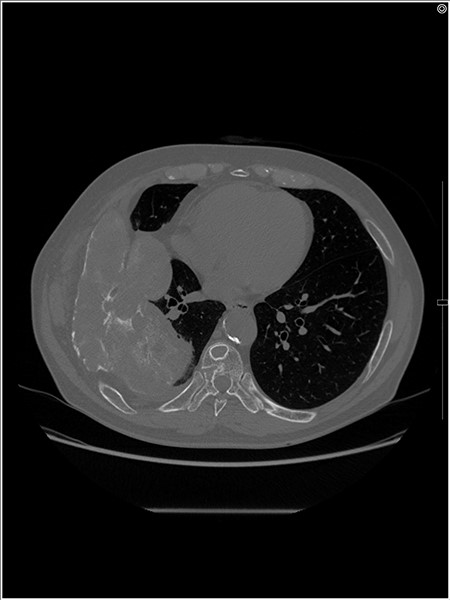

An axial CT image shows the extra-osseous tumor with calcification and cortical destruction of the right seventh rib.

A 72-year-old man was referred to our department with a suspected tumor in the right rib. An abnormal shadow in the right chest was found during screening at 50 years of age. The patient was later followed up intermittently by a general physician (Fig. 1a and b). At 72 years of age, he was referred to our department because of a suspected malignant tumor. There were neither subjective symptoms nor abnormal physical findings. A blood test revealed an elevated level for alkaline phosphatase alone at 706 U/L. A pulmonary function test showed a percent vital capacity (%VC) of 78.8%, indicating a mild restrictive impairment. Plain radiography showed a radiopaque tumor measuring 12 × 9 × 18 cm that was connected to the seventh rib in the right thoracic cavity (Fig. 1c). When compared to previous images, the tumor had gradually grown over the preceding 22 years. Computed tomography (CT) showed an extra-osseous tumor-like lesion with calcification, cortical destruction of the right seventh rib and a similar small lesion in the right ninth rib (Fig. 2). Moreover, lesions were also detected in the ninth thoracic vertebral body. Magnetic resonance imaging (MRI) revealed a lower signal intensity inside the lesion compared to the muscle on T1-weighted images and a mixture of low and high intensity on T2-weighted images, while enhancement was observed in the lower intensity area on T2-weighted images (Fig. 3a and b). Bone scintigraphy and positron emission tomography/computed tomography (PET/CT) revealed an increased uptake in the right seventh and ninth ribs and ninth vertebral body, and the right seventh rib showed a high standard uptake value at 7.67 on PET/CT (Fig. 4a and b).